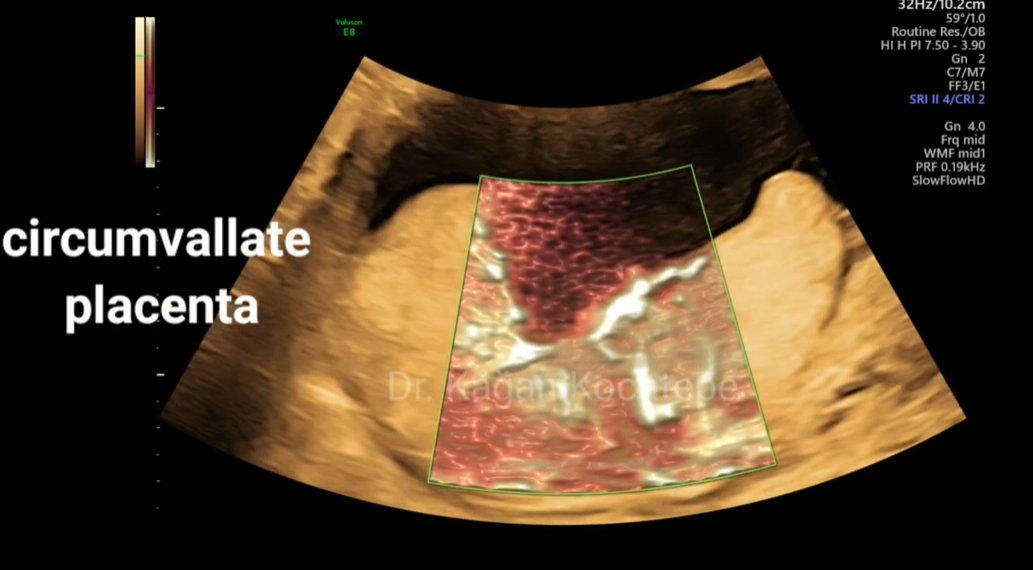

Nhau cuộn mép (Circumvallate Placenta)

16/03/2026